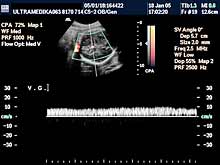

1. Arahnoidalne ciste ne bi trebalo da predstavljaju dijagnostički problem. One su avaskularne te se kolor Dopplerom (CD) ne dobija protok u njima. Ako postoji dilema koristi se kolor Power angio mod (CPA) (sl 010) koji registruje i protoke ekstremno malih brzina bez obzira na upadni ugao ultrazvučnog talasa u odnosu na krvni sud, što je osnovni preduslov za registrovanje protoka krvi, od pre 20 gidina poznatim konvencionalnim kolor Dopplerom . Mora se napomenuti da u toku pregleda u III trimestru trudnoće, jako često postoje nepovoljni uslovi za pregled (neadekvatan položaj ploda, neoptimalna količina plodove vode, debljina prednjeg trbušnog zida trudnice i položaj posteljice). U ovakvim situacijama aparati slabijih tehničkih mogućnosti, sa nižom cenom koštanja i posedovanjem klasičnog načina dobijanja ultrazvučne slike i kolor Doppler tehnike, imaju znatno ograničene dijagnostičke mogućnosti.